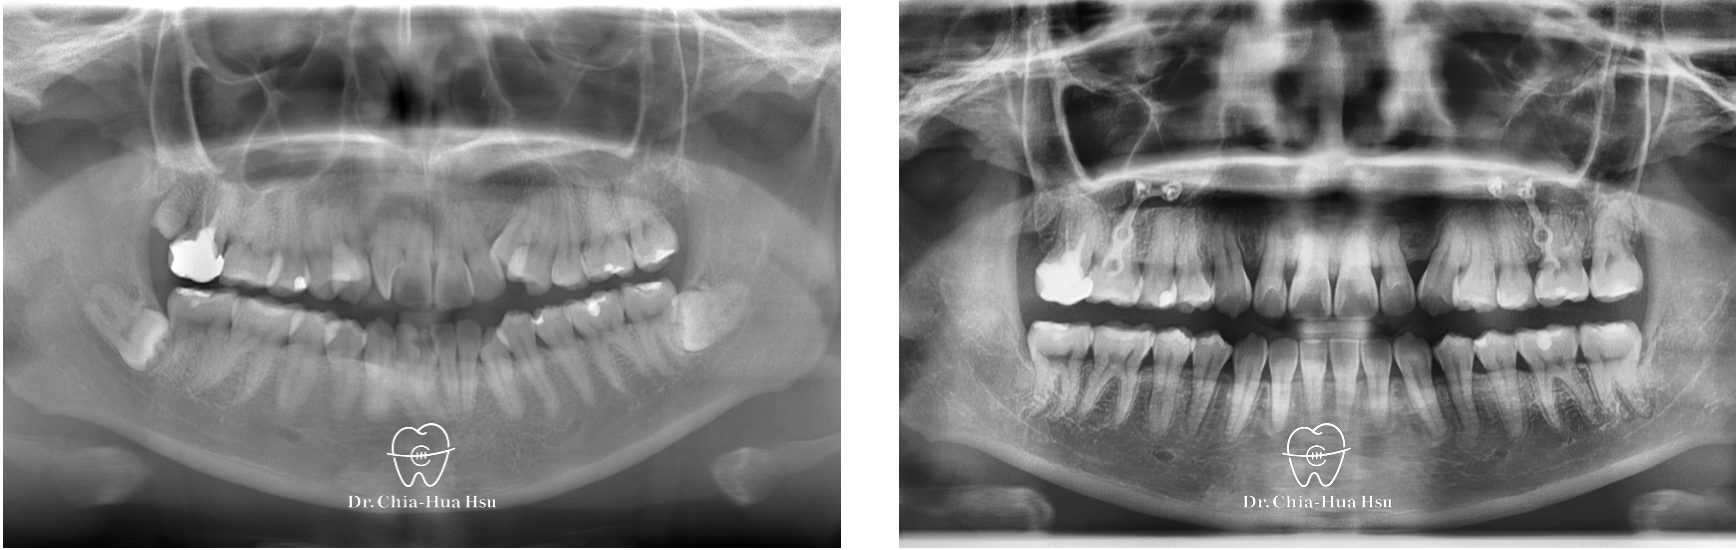

治療前

治療後

- 問題分析:患者是標準的骨骼一類咬合(Skeletal Class I)伴隨齒列擁擠。

- 治療方式:雖然患者的齒列凌亂程度甚為嚴重,但是考量到患者外觀、門牙可以往外移動一些,而且尚有智齒空間可以退後,因此最後選擇隱適美治療,不拔小臼齒,利用骨釘與骨板退後齒列,同時讓門牙向外推出去一些,並撐寬牙弓以獲得空間。